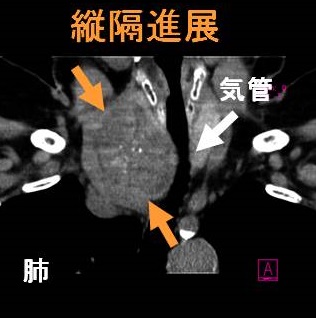

巨大甲状腺腫や高度肥満による気道狭窄で甲状腺切除手術の気道確保困難(挿管困難)が予測される場合、VV-ECMO(体外式膜型人工肺)開始後、気管支鏡を用い挿管。内臓逆位では心血管・消化器系の奇形を合併しなくても左右の反回神経の走行が逆になるため注意。巨大甲状腺腫、甲状腺癌の転移・浸潤が胸骨に及ぶ場合、胸骨切開(全切開、部分切開)/胸骨切除が必要。甲状腺手術の皮膚縫合は美容上の問題から形成外科が行う事も。甲状腺の病気があれば経皮経食道胃管挿入術(PTEG/ピーテグ)は禁忌。海外では甲状腺摘出術後の頸部創傷治癒促進と瘢痕形成抑制にPRP療法。

甲状腺手術で首の辺を切開するのは当然ですが、胸骨切開(全切開、部分切開)/胸骨切除が必要な時もあります。

- 縦隔進展する巨大甲状腺腫(縦隔内甲状腺腫 )

- 甲状腺癌の転移・浸潤が胸骨の所まで及ぶ

などの場合です。胸骨切除は大胸筋皮弁形成が必要となり、炎症による胸水貯留がおきる場合もあります。